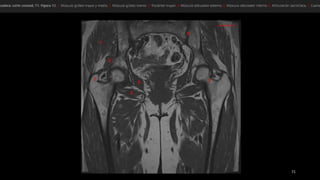

• músculo glúteo mayor (GMa)

• músculo tensor de la fascia lata (Tfl anterior y la

fascia lata (FL) situada entre ambos músculos

• «bandeleta de Massiat» (BM)

• glúteo medio (GMe) y glúteo menor (GMI)

• trocánter mayor (TM)

• músculo glúteomayor (GMa) • músculo tensor de la fascia lata (Tfl anterior y la fascia lata (FL) situada entre ambos músculos • «bandeleta de Massiat» (BM) • glúteo medio (GMe) y glúteo menor (GMI) • trocánter mayor (TM)